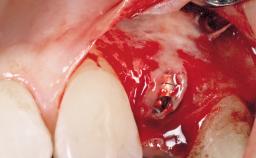

After flapless tooth extraction and a healing period of 6 weeks, a standard-diameter one-piece implant is placed. A gap between the implant and the facial bone wall is filled with autogenous bone chips harvested from the anterior nasal spine and covered with DBBM particles. Contour augmentation on the facial aspect is achieved using DBBM particles and a collagen membrane, according to the principles of guided bone regeneration (GBR). The flap is coronally repositioned for semisubmerged healing.